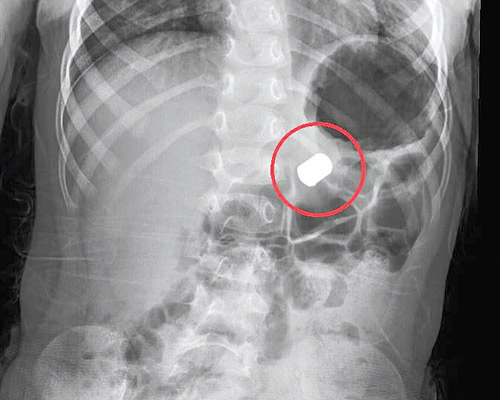

وقد تم استدعاء الأطباء المختصين الذين قاموا على الفور بعمل الفحوصات الأولية وإجراء عدد من التحاليل وأشعات (X-RAYS) ، والتي أبانت وجود 4 قطع مغناطيسية داخل الجهاز الهضمي، حيث تم وضع خطة علاجية سريعة ومناسبة لاستخراج تلك الأجسام وللحيلولة دون حدوث أية مضاعفات تنتج عن نزول تلك القطع إلى الأمعاء وما قد يسببه ذلك من مشاكل أو ثقوب داخلية.

حيث أوضحت نتائج الفحوصات الدقيقة وجود 4 قطع مغناطيسية على شكل قرص تسببت في حدوث ثقب في جدار المعدة واستقرت داخل البطانة، إذ يبلغ قطر القطعة الواحدة منها 2 سم، بعد ذلك تم وضع المحاليل الوريدية والبدء في إجراءات العلاج. ونتيجة وجود القطع المغناطيسية داخل جدار المعدة زاد الأمر صعوبة وعليه كانت الخطة قيام فريقين من استشاريي مناظير الجهاز الهضمي باستخدام مناظير الفم والفريق الثاني من استشاريي جراحة الأطفال عن طريق مناظير البطن الجراحية بالتجهيز للعملية. ومن ثم قام الفريق الطبي بالبدء في الجراحة التي استغرقت قرابة الساعة، حيث تم رؤية القطع المغناطيسية بوضوح متمركزة داخل جدار المعدة، وهو ما حدا بالأطباء التعامل بحذر ودقة ليتم السيطرة على هذه القطع واستخراجها.